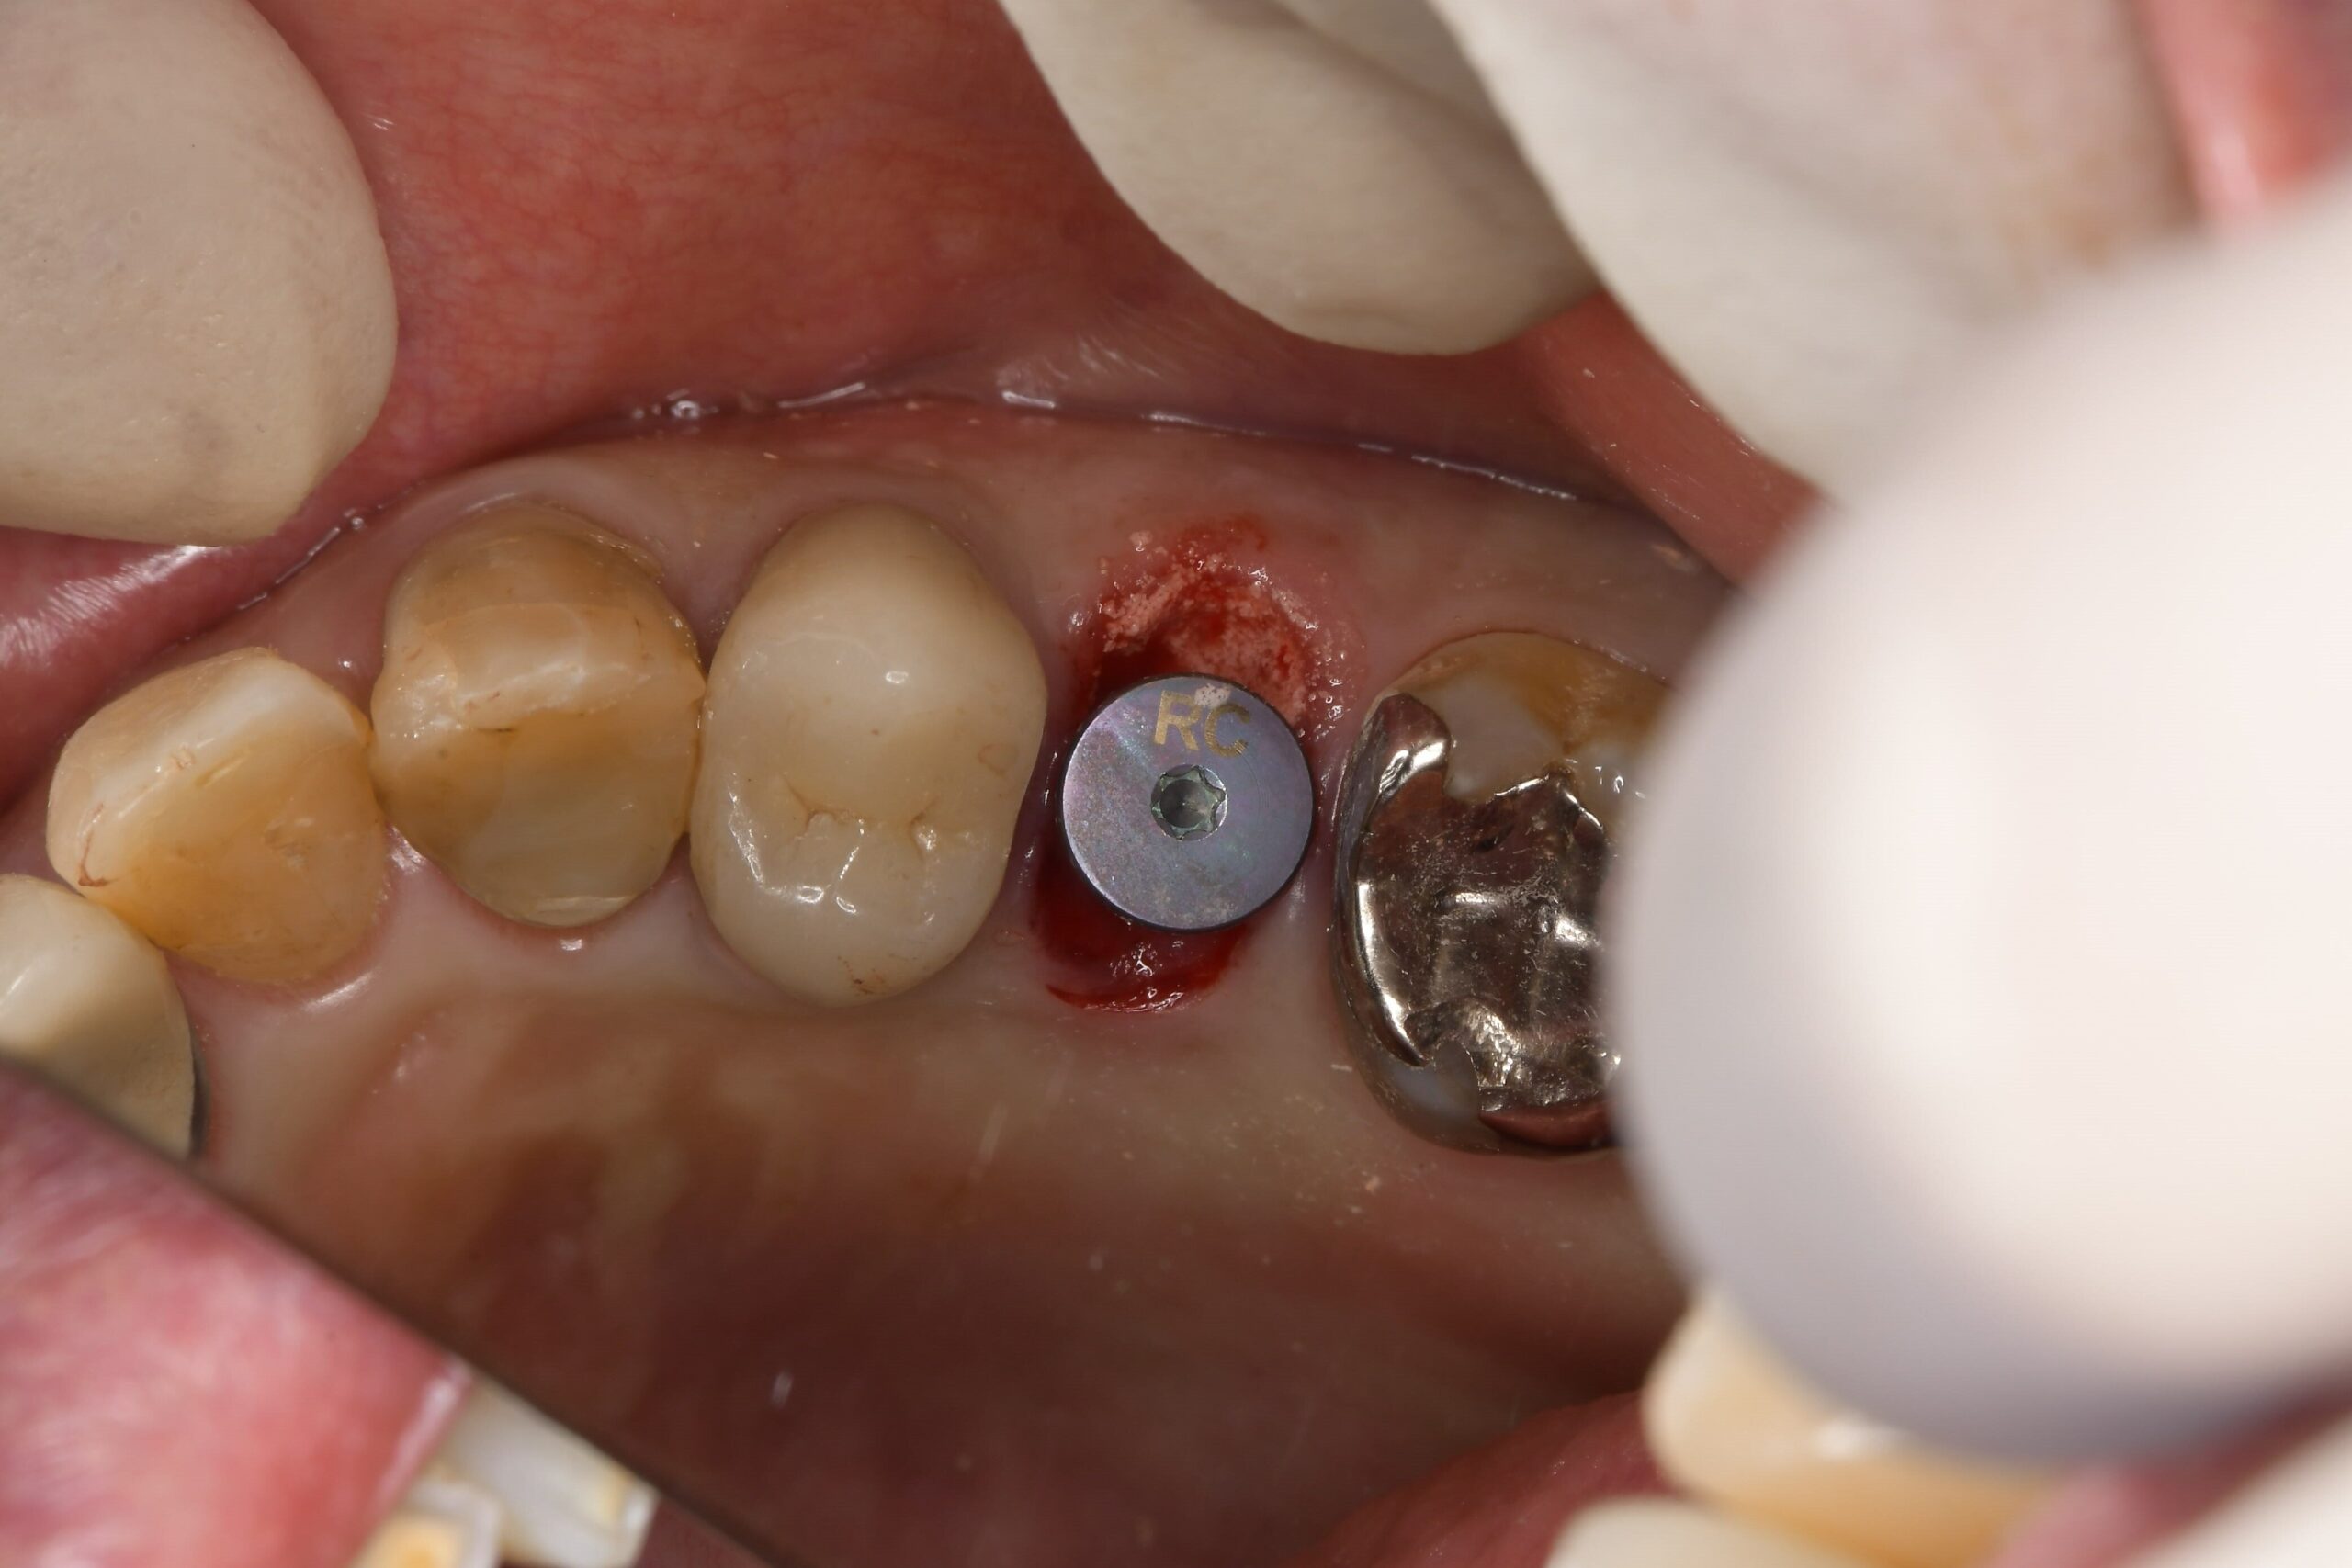

1.抜歯: 原因となっていた、割れた歯を丁寧に抜歯します。周囲の骨を傷つけないよう慎重に行います。

2.ガイド装着: 作製しておいたサージカルガイドをお口に装着します。

3.インプラント埋入: ガイドの穴に沿ってドリルを進め、インプラントを埋入します。事前のシミュレーション通りの位置に、迷いなくピンポイントで設置できるため、手術時間は比較的短く済みます。

マウスピースのような形をした手術用補助器具です。インプラントを埋め込むための穴が開いており、ドリルがブレることなく、計画通りの位置・深さにインプラントを導きます。これにより、血管や神経を傷つけるリスクを最小限に抑えます。